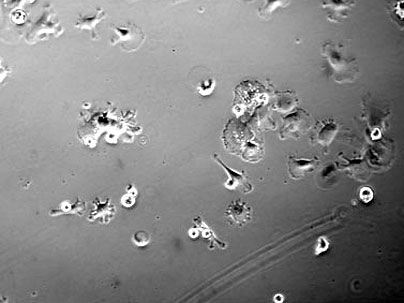

MIT researchers have discovered that treating bone marrow stem cells with a growth factor called EGF promotes their survival and growth when the EGF is tethered to a scaffold. This image shows stem cells with no EGF treatment. <a onclick="MM_openBrWindow('stem-cells-1-enlarged.html','','width=509, height=583')">